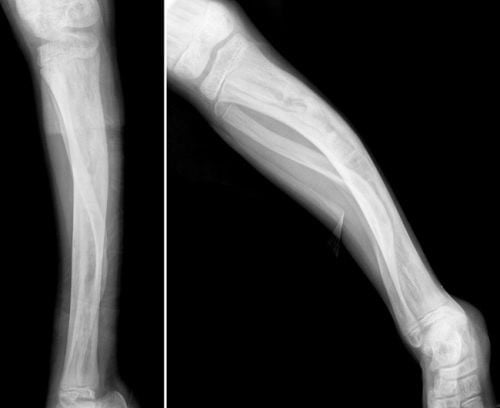

Chăm sóc bệnh nhân sau bó bột gãy xương

Bó bột là phương pháp kết xương trong gãy xương hiệu quả. Để người bệnh nhanh chóng hồi phục việc chăm sóc bệnh nhân sau bó bột gãy xương cần lưu ý những vấn đề sau. Gãy Xương Đòn Đeo Đai Số 8 Bao Lâu thì có thể Tháo được? Gãy xương chân kiêng ăn […]